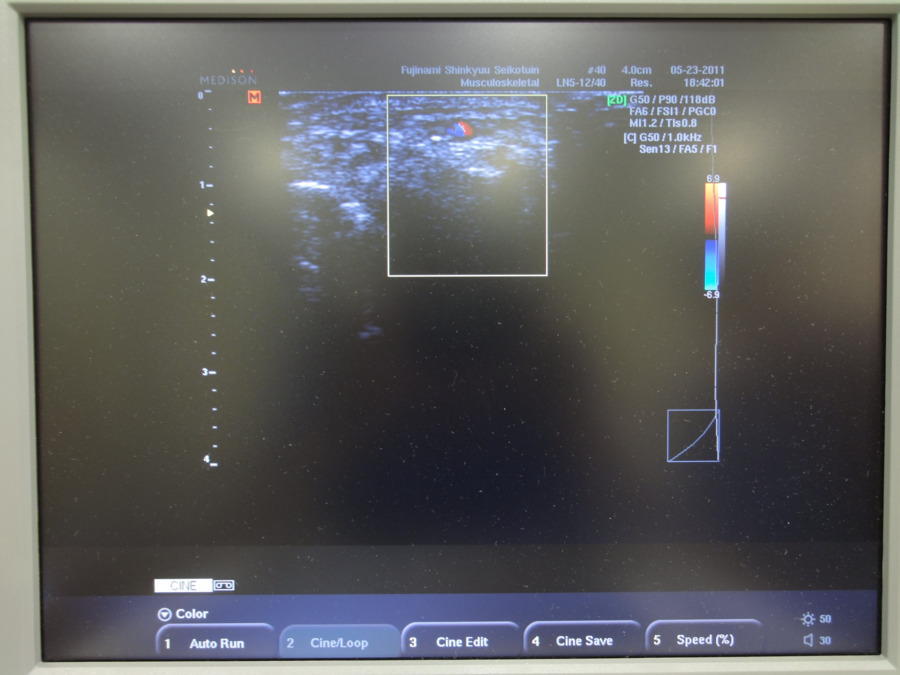

エコーがあり、外傷にも対応できます

エコーがあり、外傷にも対応できます